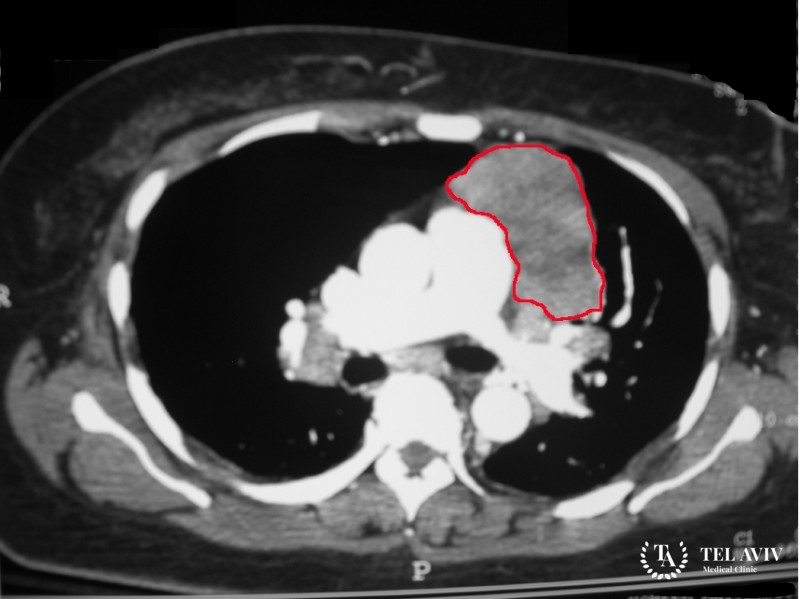

Первичные герминогенные образования в средостении – гетерогенные патологии. В основе опухолей – зародышевые клетки, принимающие активное участие в процессе формирования половой железы. Герминогенные новообразования относятся к классу редких заболеваний. В большинстве случаев патология поражает гонаду. Семиномы могут образоваться в забрюшинном пространстве, пресакральной зоне, в средостении.

- Рентгенография средостения – оптимальный, информативный метод диагностирования семиномы;